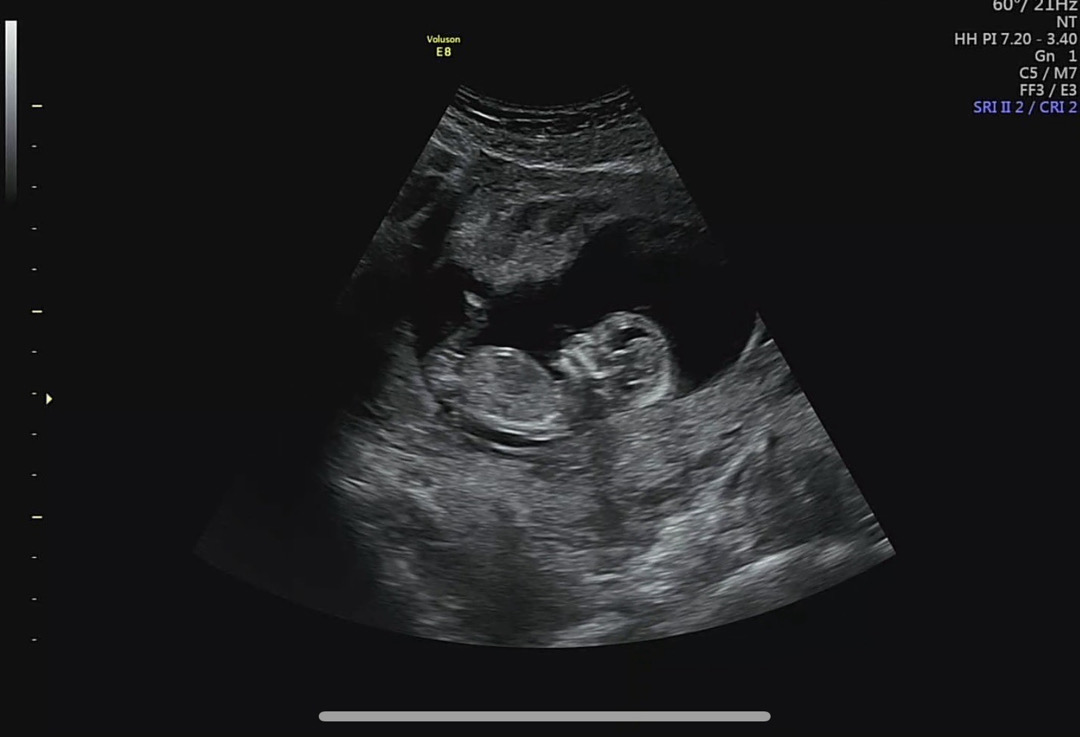

12주 4일 각도법 봐주세요!!

각도법 아무리 봐도 모르겠어요🥲